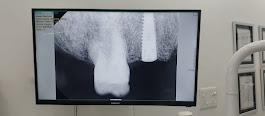

Image Gallery

Pictures That Speak